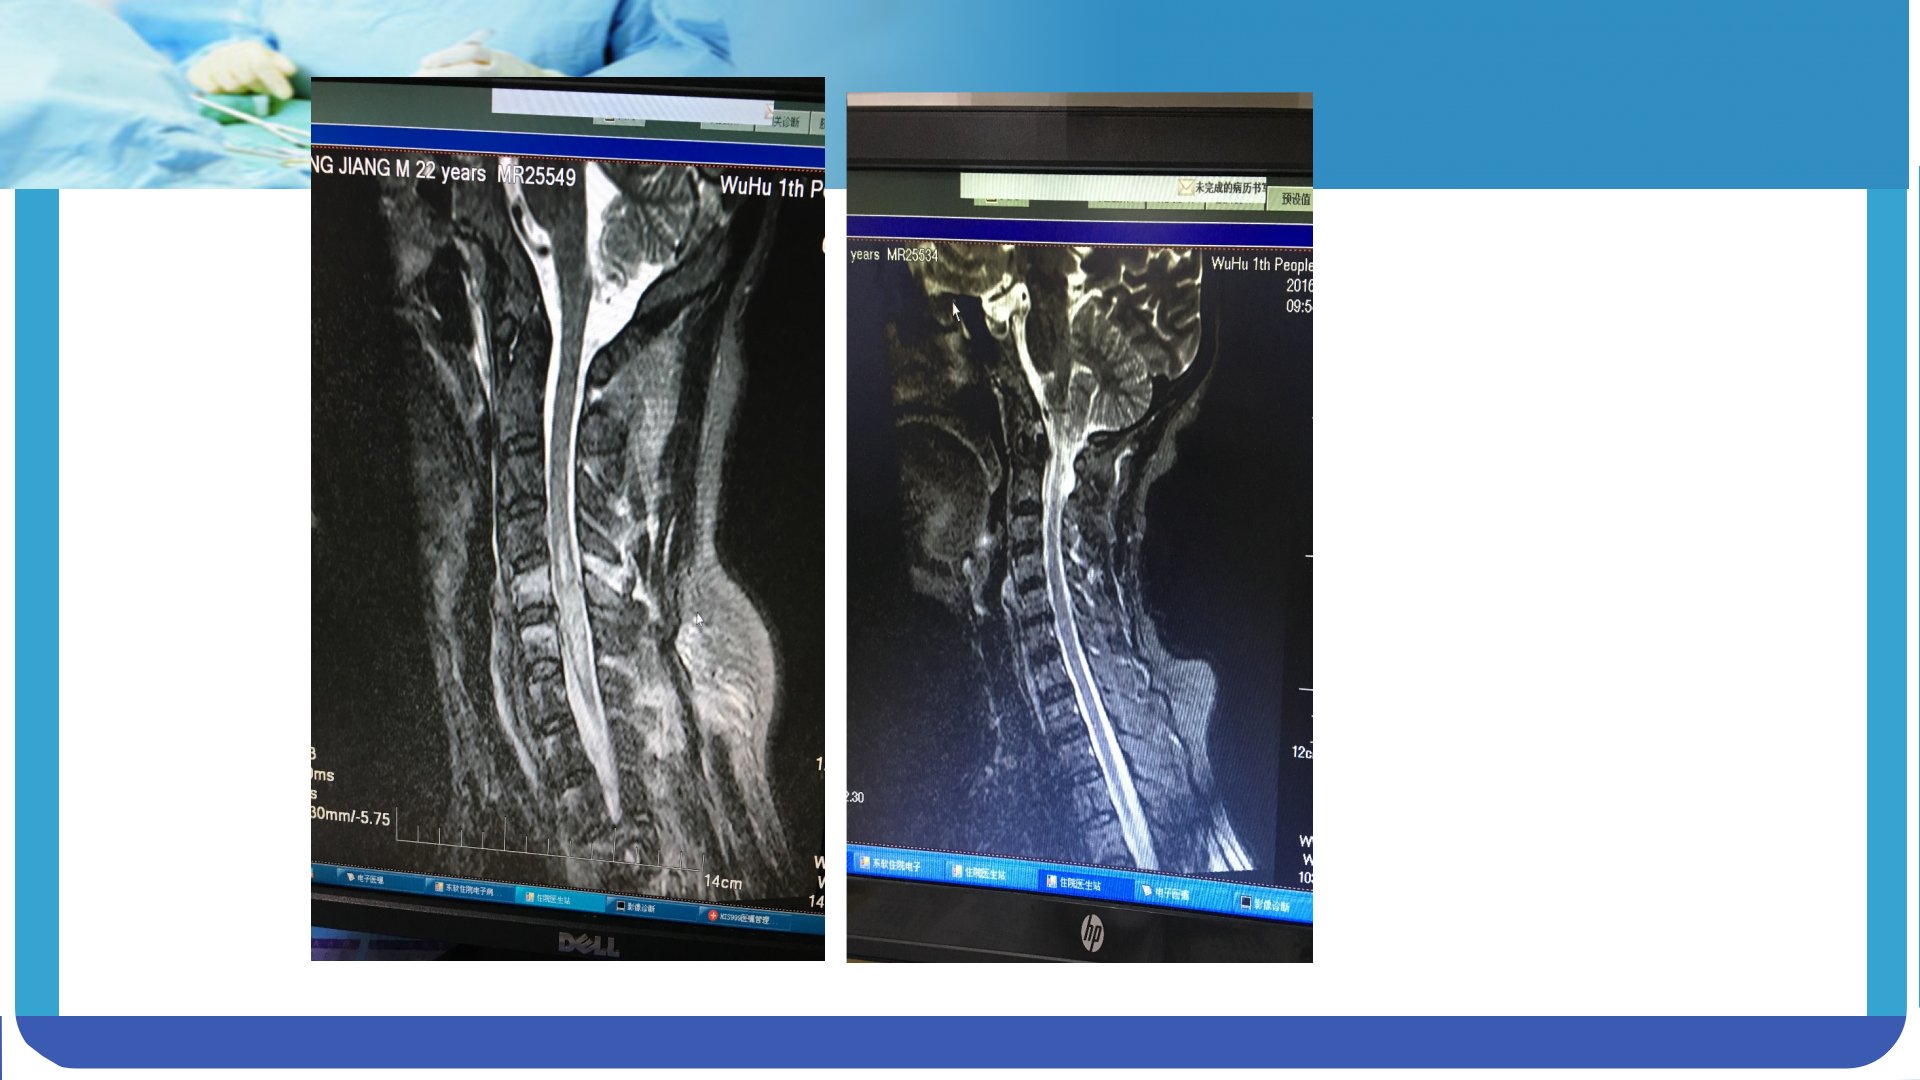

颈髓损伤护理查房摘要颈髓损伤是颈部脊髓因外伤、肿瘤、感染等因素造成的严重损伤常导致肢体感觉、运动及自主神经功能障碍。损伤分类包括闭合性和开放性脊髓损伤病理上分为原发性和继发性损伤程度上有完全性和不完全性之分。病因及机制:闭合性损伤常见于脊柱远隔部位的外力传导而开放性损伤则涉及锐器或火器造成的脊髓外露。原发性损伤直接破坏脊髓组织引发细胞水肿、酸中毒等;继发性损伤则包括脊髓水肿、椎管内出血等进一步加剧功能障碍。临床表现:依据损伤部位和程度不同患者可出现截瘫、感觉障碍、反射异常及括约肌功能障碍等症状。高颈髓损伤导致呼吸困难和四肢瘫痪中颈髓损伤引发四肢瘫痪和根痛下颈髓损伤则导致四肢瘫和上肢下运动神经元损害。检查与诊断:通过X线、CT、MRI及腰椎穿刺等辅助检查确定损伤性质和程度。急救时需保持脊柱稳定避免二次损伤。治疗包括颅骨牵引、药物治疗、手术治疗及对症治疗。护理评估:评估患者健康史、身体状况、心理社会状况制定个性化护理计划。护理问题包括焦虑、躯体移动障碍、呼吸型态异常、清理呼吸道无效、感染风险、体温过高及便秘等。针对这些问题采取心理支持、功能锻炼指导、呼吸管理、呼吸道清理、感染控制、体温调节